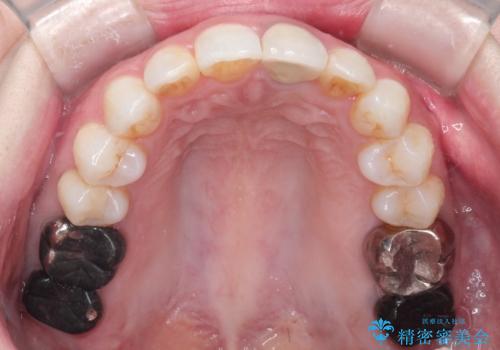

インビザラインによる非抜歯矯正 ガタガタな歯並びを整った歯並びへ

- 上下の全体的ながたつきが気になるとのことで来院されました。

全体的に歯と歯の間にわずかに隙間を作り、歯を並べました。